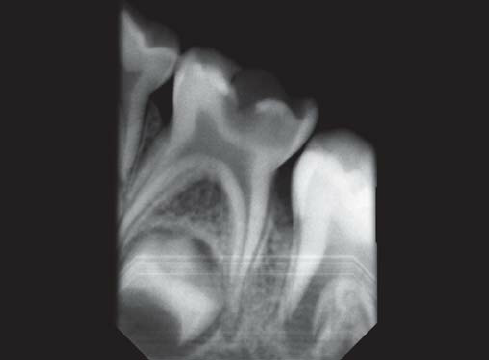

• Thorough examination and digital X-rays to assess the extent of damage.